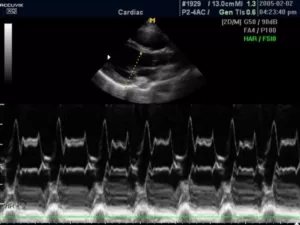

М-режим (отраженный импульсный режим)

M-mode («motion» — движение) — одномерная регистрация отраженного эхосигнала, применяющаяся в кардиологии для изучения сократительной способности миокарда, клапанного аппарата, оценки изменения размеров полостей в систолическую и диастолическую фазы.

В данном режиме оператор сканирует кардиальные структуры только вдоль одной оси. Информация о сигналах с различных глубин изображается в виде отметок различной яркости вдоль вертикальной линии на дисплее. Следующему зондированию соответствует другая линия, расположенная правее предыдущей. В ходе перемещения столбца с каждым новым сканированием записывается двухмерная М-эхограмма.

Существует несколько типов М-режима:

·      M-mode (стандартный): предполагает получение одномерного изображения;

9.jpg

·      Color M-mode (цветной): сочетает стандартный режим и цветовое допплеровское картирование;

11.jpg

·      Free-angle M-mode (анатомический): позволяет произвольно выставлять направление зондирования и визуализировать кардиальные структуры под различным углом.

12.jpg

При неправильном расположении курсора все параметры могут быть завышены, что приведет к неправильной интерпретации полученных данных. Поэтому диагностика в М-режиме требует строгого соблюдения правильной позиции сканирования.

Классический М-режим имеется во всех современных ИЗИ аппаратах, анатомический режим представлен в устройствах более высокого класса. Специальные датчики для обследования в М-режиме не применяются, регистрация М-эхограмм осуществляется датчиками для В-сканирования.